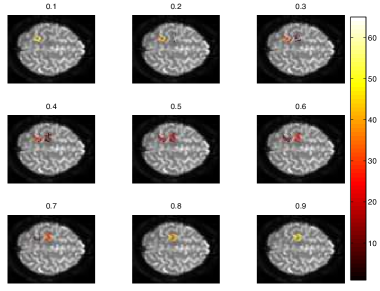

3.1.2 Gaussian Process Regression

As mentioned above, the simulated image data was generated for N=7𝑁7N=7 behavioural scores, representing 777 subjects with unique neuro-psychological assessment values. For each subject, a voxel-wise general linear model was fitted, resulting in parameter estimate β^vsubscript^𝛽𝑣\hat{\beta}_{v} for voxel location v𝑣v. This estimate was subsequently converted to a z-score and so the data is reduced to one z-score for each voxel. A voxel-wise Gaussian process model, with squared-exponential plus noise covariance function, was then adapted to the image features.

The GPs were evaluated at the unobserved factor values (0.4,0.5,0.60.40.50.60.4,0.5,0.6) to produce posterior mean and variance images. E.g. at values around 0.50.50.5, see figure (2a), the model suggests two active regions. However, the variance image, see figure (2b) also indicates a high degree of uncertainty. This variance may be used to guide future fMRI experiments. A confirmation of an actual measurement at factor value of 0.50.50.5, say, would suggest a gradual change of cognitive function with behaviour, whilst a refutation suggests a sudden transition of function.

Refer to caption

(a) The predictive mean

(b) The predictive variance

Figure 2: Simulation of a Gaussian process prediction of z-scores given a hypothetical behavioural measure (normalised between 01010-1).